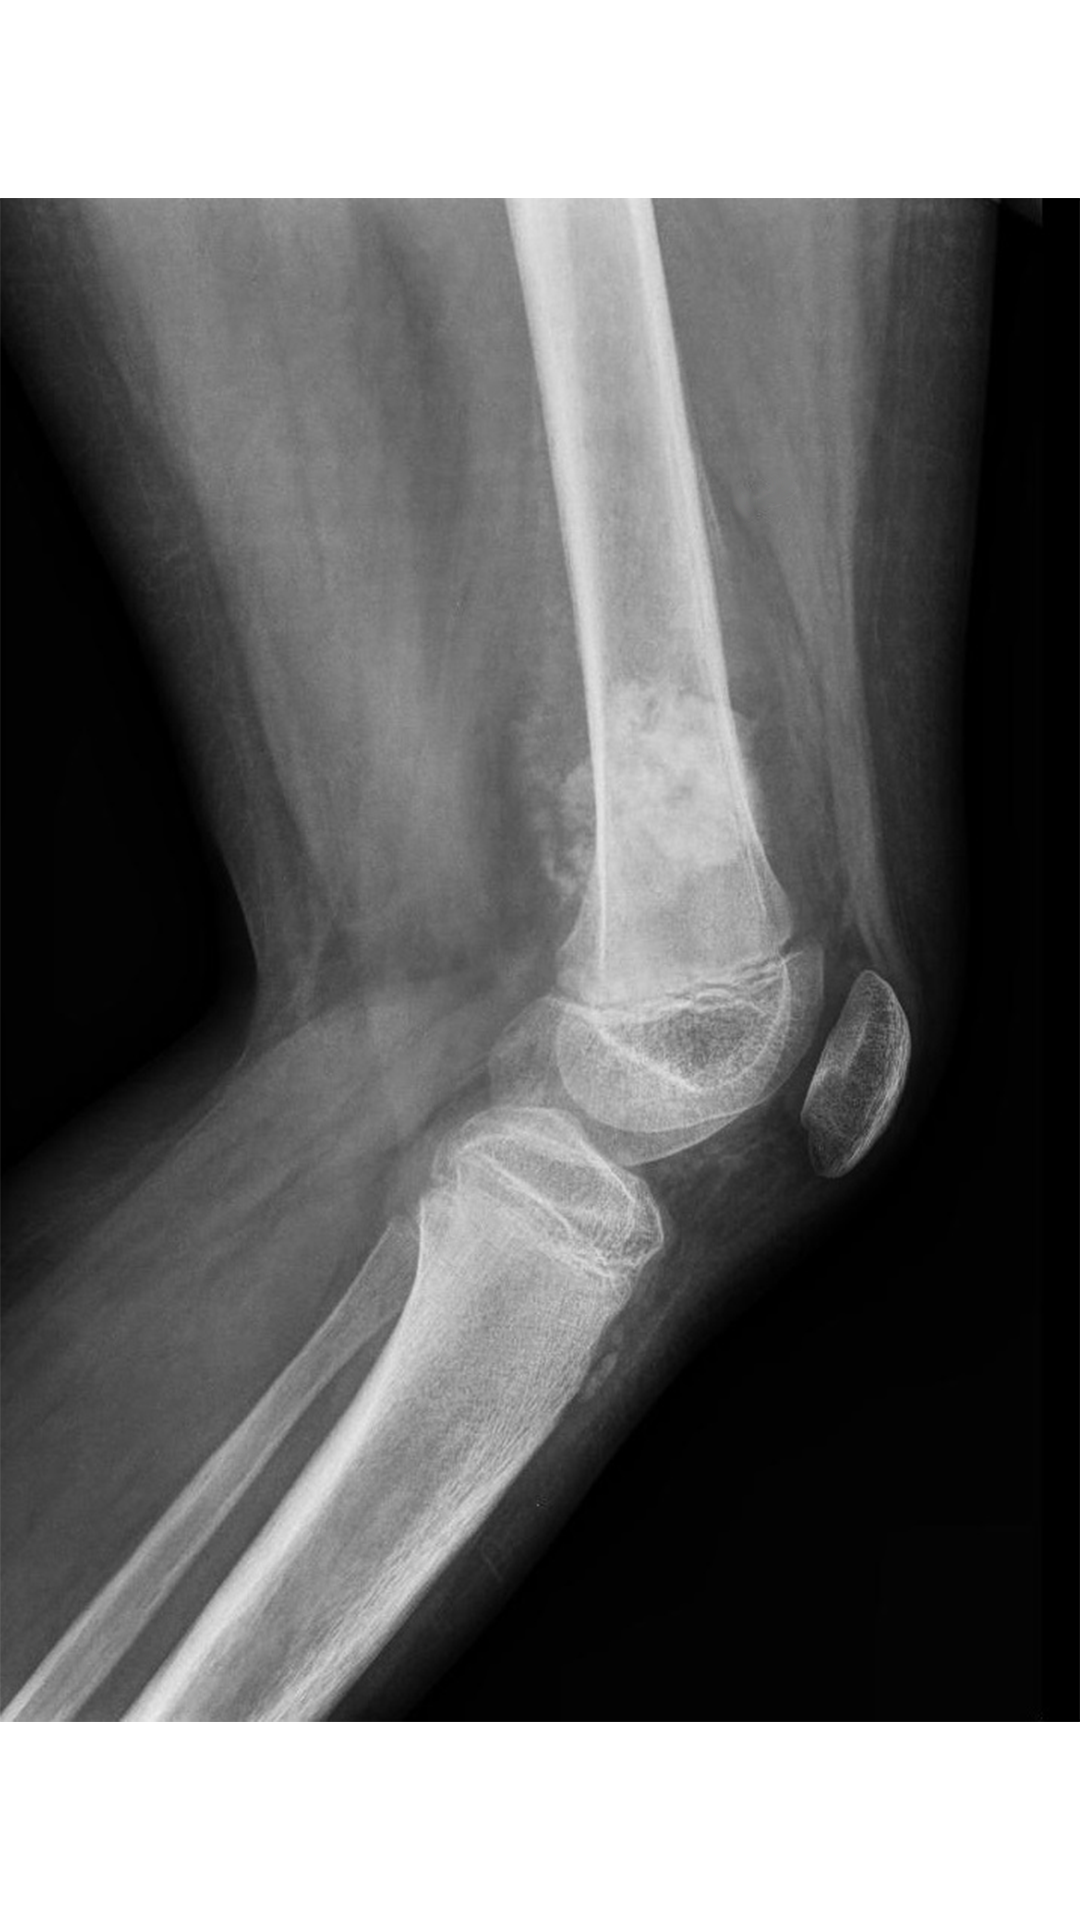

Vous vous occupez de Mathéo, 15 ans, hospitalisé dans votre service depuis ce matin pour exploration d’une masse fémorale douloureuse avec boiterie depuis 3 mois.

Votre examen clinique est normal en dehors d’une masse douloureuse à la palpation de l’extrémité inférieure du fémur gauche.

Vous faites réaliser une imagerie que voici.